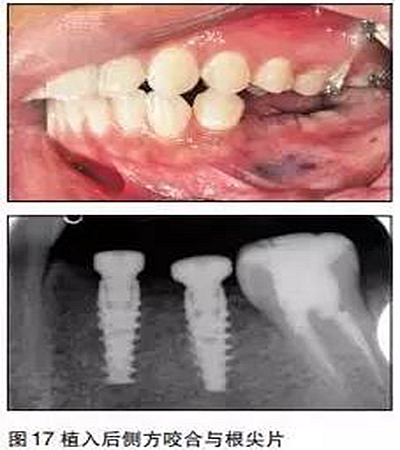

③用骨鑿去除部分牙槽嵴頂骨質(zhì),球鉆定位,逐級備洞,植入2枚NobelActivie4.3×10mm種植體,植體植入初期穩(wěn)定性35N;

④上愈合基臺,一期縫合。

三個月后

采用閉口印模法取模,比色,送技工中心制作。

口內(nèi)就位

最后修復(fù)體在口內(nèi)就位,35N鎖緊螺絲,封閉螺絲口,納米樹脂充填螺絲開口,調(diào)牙合,拋光完成。